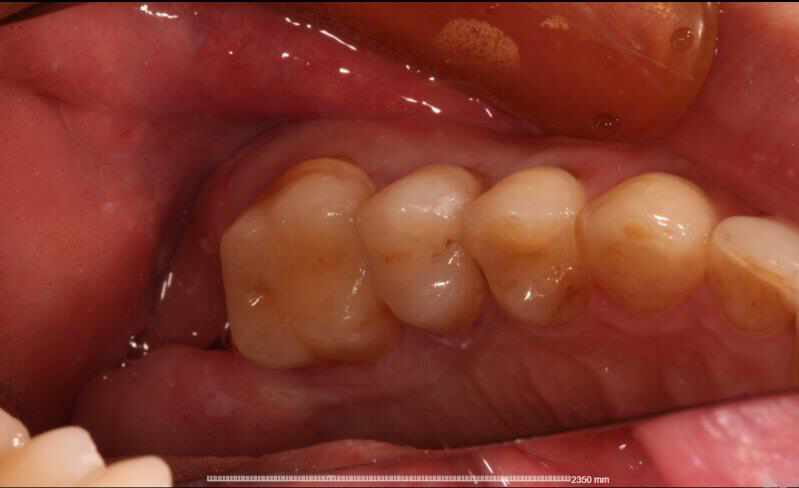

今天给大家分享一个后牙嵌体即刻修复病例。

患者中年男性,右上5、6号牙邻接处龋坏,虽然表面没有明显龋坏,但釉质下可见低密度阴影,去龋过程中见釉质下大面积龋坏。由于龋坏面积较大,且位置处在邻接处,传统补牙强度较弱,所以我们建议这位患者采用嵌体修复的方式,一日就诊,一次搞定。